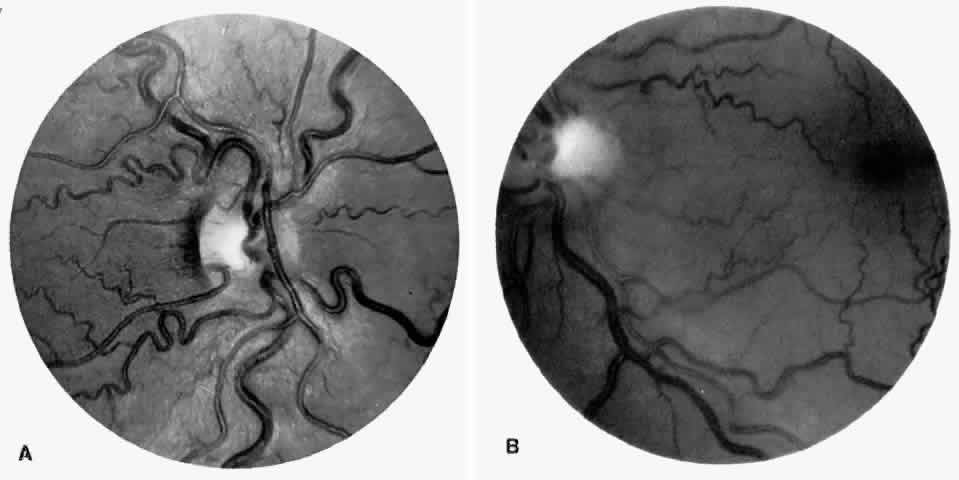

Vascular Tortuosity

Dilation and tortuosity of the retinal veins was one of the first recognized abnormalities of sickle cell eye disease. Although it is not pathognomonic of sickle cell disease, it reportedly occurs in up to 47% of patients with homozygous sickle cell anemia and 32% of patients with SC disease (Fig. 4).70 The significance of this venous tortuosity is unknown, and the incidence does not appear to be related to age.71

Fig. 4. A. Generalized vascular tortuosity, predominantly venous, in a patient with homozygous sickle cell anemia. B. Localized macular venous tortuosity in a patient with SC disease.